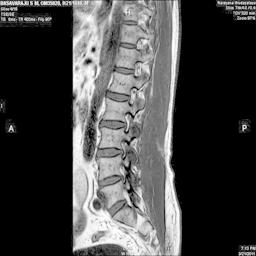

The developed algorithm presented in the previous section was coded using Matlab Version 8.0. The experiment was conducted by considering poor quality spinal cord images of having various lesions. The first column of Fig. 4 shows the axial view of neck spinal cord images of size pixels, respectively. The second column of Fig. 4 presents the same images enhanced using histogram equalization. As is evident from the results presented, the histogram equalization method performs global image enhancement operation which improves the contrast of an image but at the cost loss in image details. The third column of Fig. 4 shows the MSR based spinal cord image enhancement. It can be seen that from the result presented, MSR scheme improves the details that are not clearly visible in histogram equalization technique. In general, image enhancement achieved by MSR method is better compared to histogram equalization. However, the MSR method voilates gray world assumption. Therefore, the image enhanced by this scheme appears to be grayish. Although, numerous work have been reported for solving the problem due to gray world voilation, no work seems to developed for complete elimination.

The fourth column of Fig. 4 shows the image enhanced using Chao et al. []. It can be seen from the results presented that the reconstructed images of Chao’s method have black spots. The appearance of these dark patches degrades the visual quality of the enhanced image. The image enhanced using proposed multirate multiscale retinex image enhancement method presented in the fifth column of Fig. 4, overcomes the drawback of the Chao’s method. As we can see from the simulation results, image enhancement achieved by the proposed method has improved details with significant contrast enhancement. The enhanced images from the proposed method provides information to physicians, radiologists and researchers for various types of pathology detection.